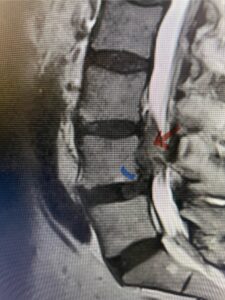

This 54-year-old morbidly obese female presents with progressive back and leg pain and quadriceps weakness. She had no diabetes. She failed all means of conservative management including physical therapy and epidural injections. On imaging she had severe stenosis at L3-4 with a disc protrusion and a slight grade 1 spondylolisthesis at L3-4 (Fig 1). We performed dynamic lumbar x-rays which demonstrated instability at L3-4 and L4-5 (Fig 2). The patient wished to have surgery. We performed an L2-4 decompressive laminectomy and L3-5 in situ fusion because of her instability. Post operatively the patient had relief of leg pain, although the patient was slow to mobilize.

Fig 1b: Axial lumbar T2-weighted MRI demonstrating severe lumbar stenosis (red dot)